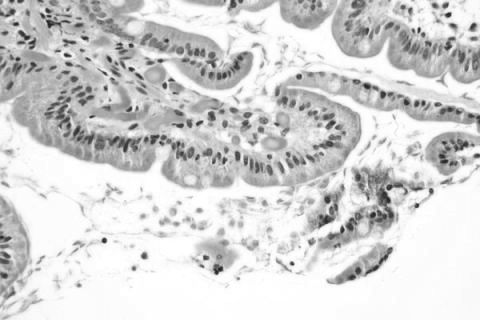

Що таке лямбліоз? Збудником хвороби є найпростіші мікроби, що паразитують в організмі людини. Джерелом часто є людина-носій, інвазірованний лямбліями.